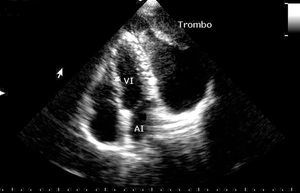

Con este enfoque fue remitida a nuestro laboratorio de ecocardiografía. Al comenzar el estudio encontramos una imagen ecolúcida posterior al ventrículo izquierdo (VI), así como hallazgos de una estenosis mitral ligera. Al continuar los cortes ecocardiográficos desde la visión de 4 cámaras apical (fig. 1), la imagen ecolúcida vista anteriormente se proyectaba además, lateral al VI, y se logró demostrar mediante eco-Doppler codificada a color y Doppler pulsado la comunicación de ésta con la aurícula izquierda (AI). Otro dato que ayudó a confirmar el diagnóstico fue la aparición de contraste espontáneo en el interior de la cavidad y la presencia de trombos dentro de ésta.

Fig. 1. Visión de 4 cámaras apical en la que se observa la relación del ventrículo izquierdo (VI) y la aurícula izquierda (AI) con el aneurisma de la orejuela que contiene trombos en su interior.

Con ese diagnóstico fue remitida a un centro cardioquirúrgico, donde fue intervenida con éxito de un aneurisma gigante de la orejuela de la AI.